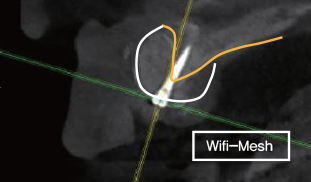

Wifi-Mesh와 BOSS Screw를 이용한 수직 골 증대

② BOSS Screw 중앙에 고정

③ 골이식 시행

④ Cover를 이용하여, Wifi-Mesh를 Screw에 장착